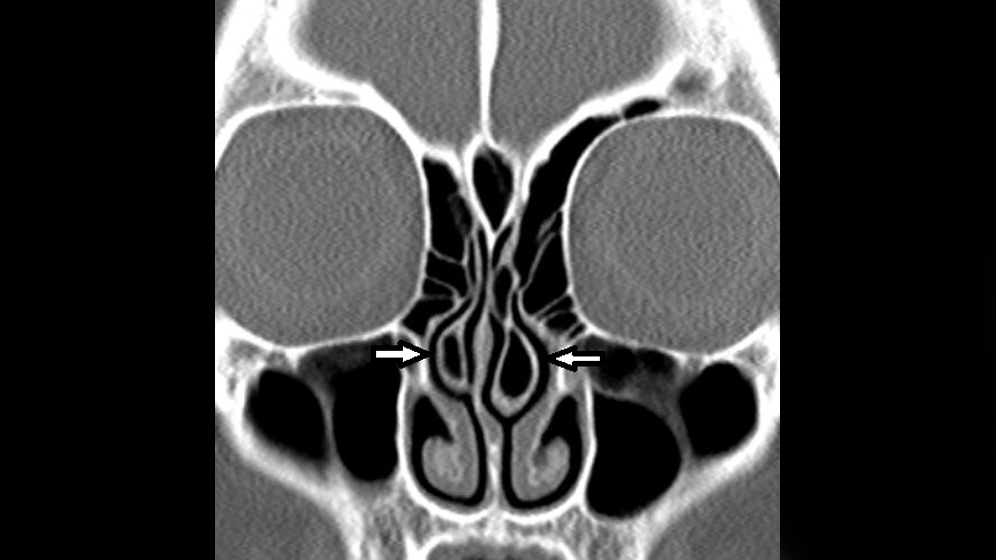

Skelettale Veränderungen 3.10: Concha bullosa - MT-Dialog

Concha Bullosa • Medizinisches Portal de.MEDtube.net